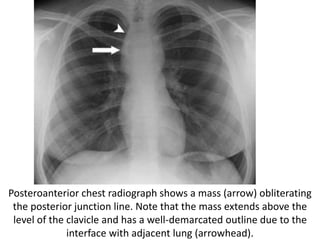

Posteroanterior chest radiograph shows a mass (arrow) obliterating

the posterior junction line. Note that the mass extends above the

level of the clavicle and has a well-demarcated outline due to the

interface with adjacent lung (arrowhead).

CT scan helps confirm the posterior location of the mass (arrow),

which proved to be a bronchogenic cyst.